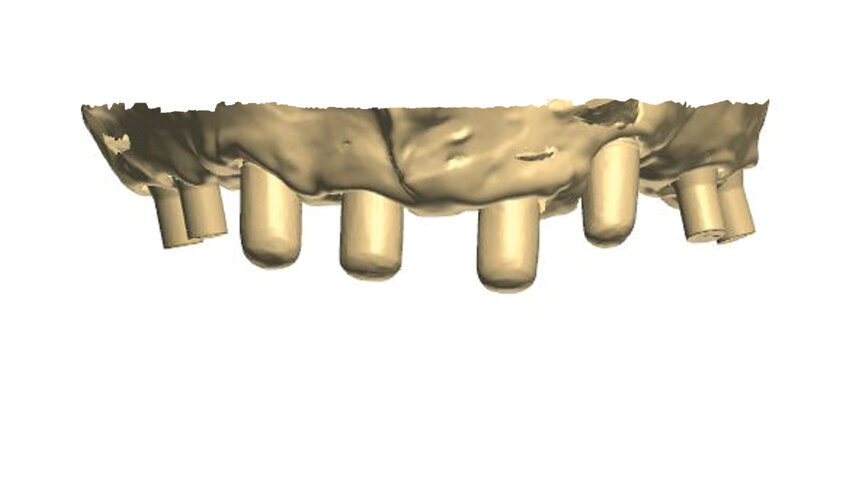

Fig. 1: A virtual image of a scanned model with abutments and telescopic crowns.

Fig. 5: Design of the framework visible from the palatal side. Visible abutments prior to the placement of telescopic crowns at the frontal section with abutments to be attached by

means of screws at the lateral section.

In order to prepare the bridge, a model was scanned and transferred onto a computer using software to design the bar (Fig. 1). The bar was designed by using special software in such a way that the whole design was transparent in the first phase so that the location of abutments and the position of the telescopic abutments at the frontal section could be visible (Fig. 2).

The patient must first approve the wax-up, in aesthetical and functional terms (Fig. 4). A computer programme for designing such constructions provides us with the possibility of viewing and designing the bar from all angles. Figures 5 to 9 show some exemplary prints of the views visible from the occlusal surface. Having finished the designing process, the bar should be visually inspected from the intragingival side (Fig. 10).